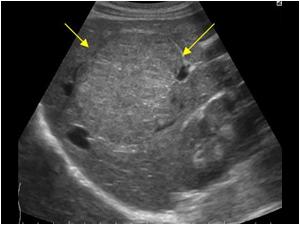

Polycystic Liver